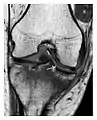

c

Figure 1: A 56-year-old woman presenting with left knee pain after a fall. (a) Initial anteroposterior radiograph was considered normal, however, subtle cortical disruption of the anterior rim of the medial tibial plateau, medial to the tibial spine, is noted (arrow). (b) Coronal T1-weighted MRI confirms the cortical disruption (arrow) and shows extensive fracture through the proximal tibia. (c) Coronal proton density-weighted image with fat saturation shows extensive edema in the subchondral bone. Note also hypersignal adjacent to the medial collateral ligament corresponding to a grade I sprain (arrowheads).[1]